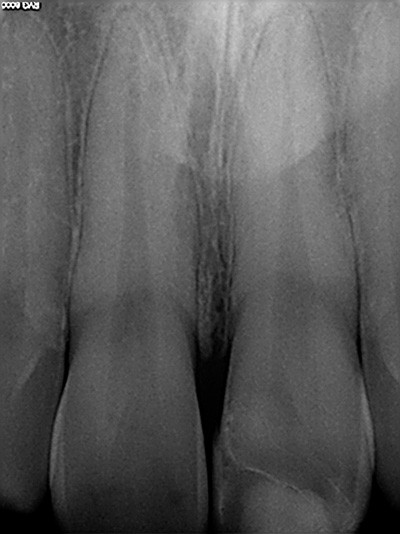

2. Situation après dépose du composite et mise en place du champ opératoire. On observe de nombreuses fêlures amélaires sur la 11 et sur la dent à restaurer.

3. En plaçant les flashs différemment, on voit moins les fêlures, mais on perçoit beaucoup mieux la texture de surface à reproduire ; c’est là que se trouve le vrai challenge !